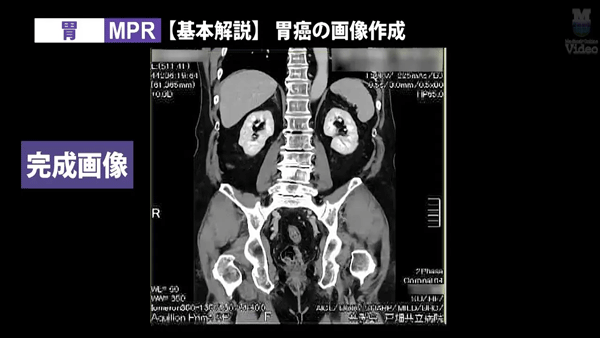

実際の作業画面を見ながら学べる、実践的な技術解説動画。 今回は「胸郭出口症候群(TOS)」および「胃」をテーマに、CT撮影から3D画像作成までの流れをわかりやすく紹介しています。

監修:山本晃義先生(戸畑共立病院) 実演・解説:田原琢朗先生 |